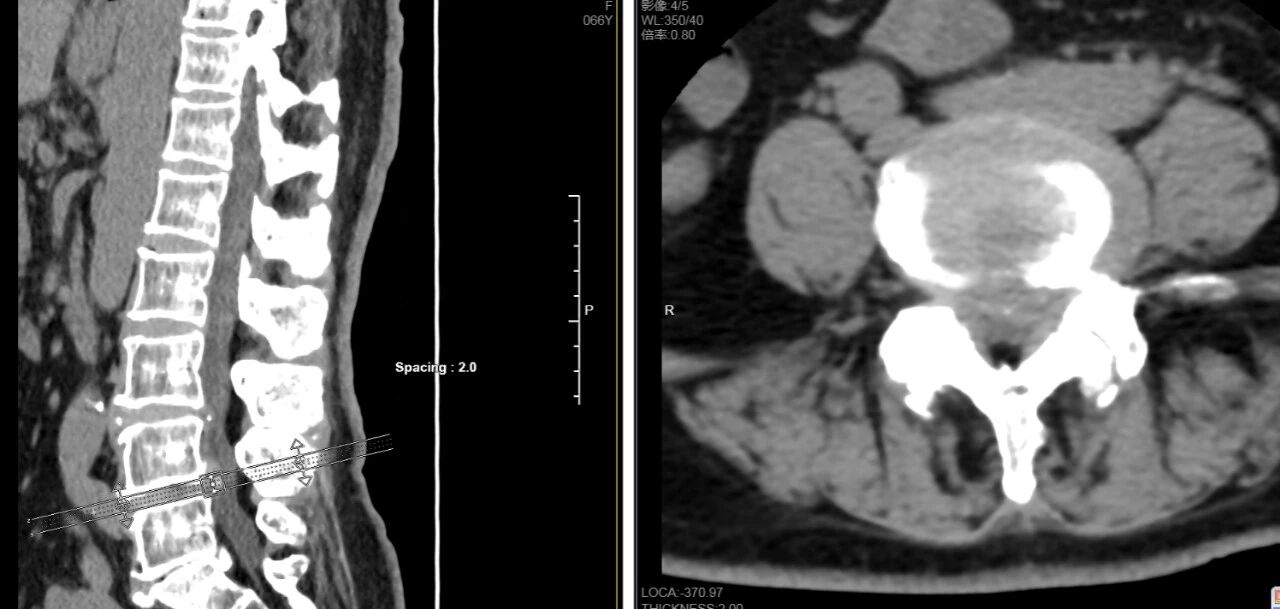

顾女士长期被腰椎间盘脱出导致臀部及左下肢的放射性疼痛缠扰,她辗转多家医院,尝试过多种保守治疗,症状却愈发严重,不仅让她“坐立难安”,生活质量也大打折扣。近日,深受病痛之苦的顾女士慕名来到南通市第三人民医院脊柱外科,经腰椎CT及MRI检查,其L4—L5椎间盘突出,神经根受压严重,综合评估目前仅靠保守治疗已难以解决病痛的折磨,脊柱外科专家团队最终决定采用业内领先的AUSS微创手术为患者解除病痛。

术中,在脊柱外科专家李玉前主任医师的技术指导下,朱敏主任医师、王震副主任医师、薛华伟副主任医师等团队成员首先借助C臂机精准定位L4—L5病变节段,于腰部切开不到2cm的微小创口,接着,在内镜高清视野下,熟练运用磨钻、射频消融刀等精密器械,精准磨除增生骨质、切除肥厚黄韧带,对神经根进行减压松解,完整摘除突出的髓核组织。专家团队凭借丰富的临床经验和娴熟的手术操作,整个过程“行云流水”、一气呵成,在精准切除病灶的同时有效避免了对周边组织的损伤,出血量不到50mL。